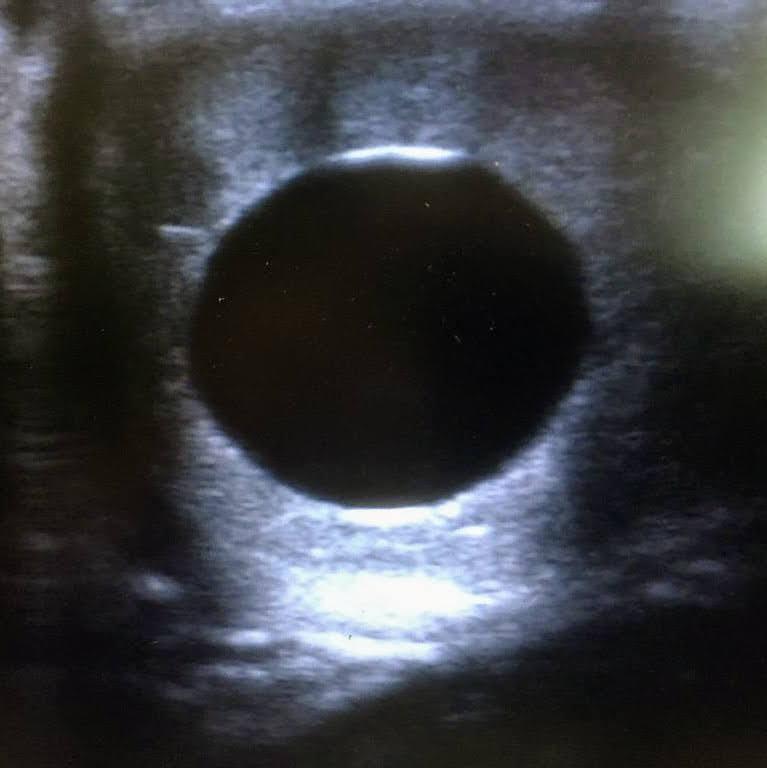

diagnostic de gestation positif chez une jument 15 jours après son insémination